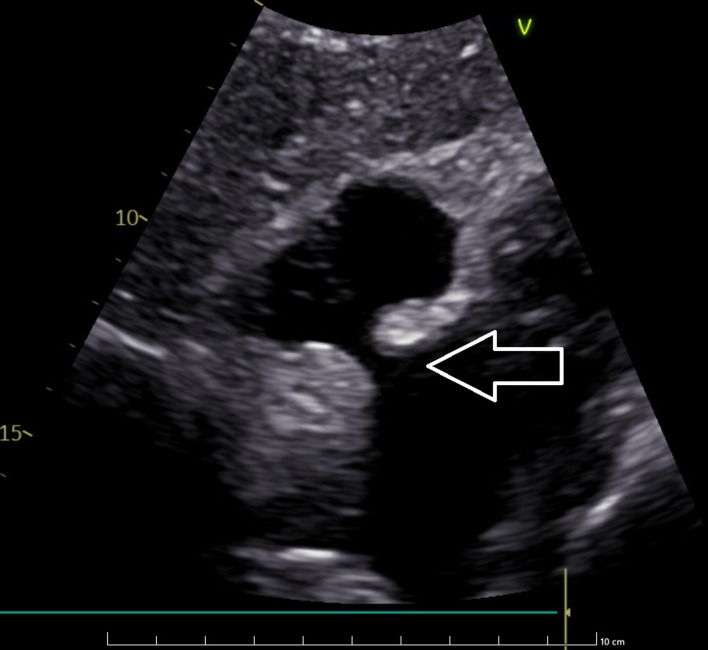

富含脂质的脂肪组织在房间隔(IAS)内异常堆积是房间隔脂肪瘤性肥厚(LHIS)的特征,这是一种相对罕见的病症。要准确鉴别 LHIS,必须识别 IAS 的特征性 "哑铃 "形状。在此,我们介绍了一例 59 岁女性的病例,她被怀疑患有心脏肌瘤,随后住进了我院。经胸超声心动图显示,患者的 IAS 在卵圆孔区域没有增厚,IAS 的基底和穹隆部分呈高回声结构。心脏计算机断层扫描(CT)发现,位于卵圆孔前方的 IAS 中有一个异常肿块,但未浸润卵圆孔。心脏磁共振成像(MRI)证实,IAS 内有大量脂肪沉积,卵圆孔窝未受影响,这与最初的检查结果一致。患者出院回家后,建议定期到心脏病学门诊进行 LHIS 监测。文章介绍了 LHIS 在连续诊断模式中的可视化表现,总结了 LHIS 的实际知识,并根据现有的成像方法对患者进行正确的 LHIS 诊断。

The abnormal accumulation of lipid-rich adipose tissue within the interatrial septum (IAS) is the hallmark of lipomatous hypertrophy of the interatrial septum (LHIS), a relatively rare medical condition. To accurately distinguish LHIS, it is essential to recognize the characteristic "dumbbell" shape of IAS. Here, we present a case of a 59-year-old woman who was suspected of having cardiac myxoma and was subsequently admitted to our hospital. Transthoracic echocardiography of the patient showed that the IAS had a lack of thickening in the region of the foramen ovale and a hyperechogenic structure in the basal and vault portions of IAS. An abnormal mass located in the IAS anterior to the foramen ovale and not infiltrating the foramen ovale was discovered by computed tomography (CT) scan of the heart. The cardiac magnetic resonance imaging (MRI) confirmed the presence of significant fat deposition within the IAS with sparing of the fossa ovalis, which was consistent with the initial findings. The patient was discharged home with the recommendation of regular visits to the cardiology outpatient clinic for LHIS monitoring. The article presents the visualization of LHIS in consecutive diagnostic modalities, summarizes the actual knowledge of LHIS, and enables proper LHIS diagnosis in patients based on available imaging methods.